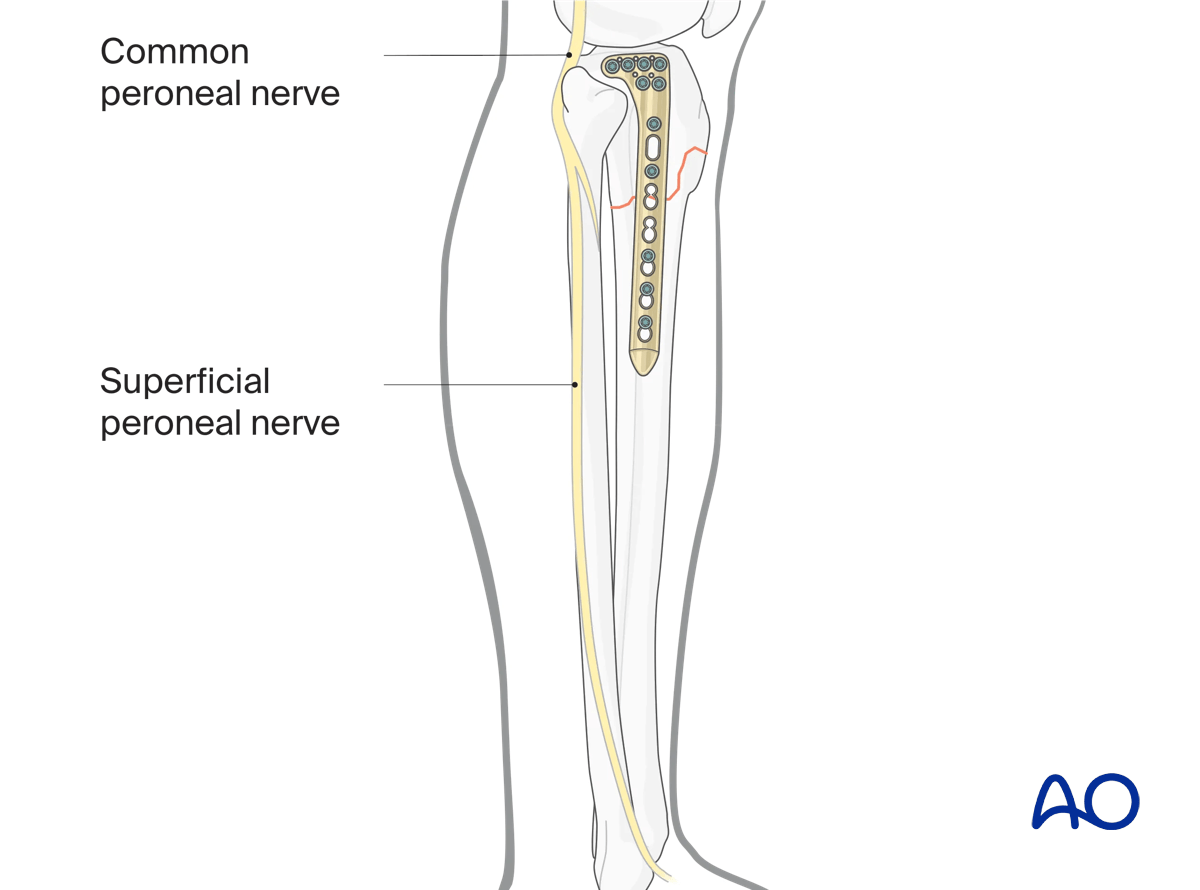

Superficial peroneal nerve

The superficial peroneal nerve is a structure at risk when plating reaches the distal quarter of the tibia laterally. When using percutaneous techniques in this region, a slightly elongated distal incision is useful both to check plate location and avoid damage to the superficial peroneal nerve.

Plate location and rotation determine (fixed angle) locking screw trajectory. Inadvertent internal rotation of the plate risks premature posterior extrusion and neurovascular compromise.

Variable angle locking designs allow for slight changes in screw trajectory if necessary.